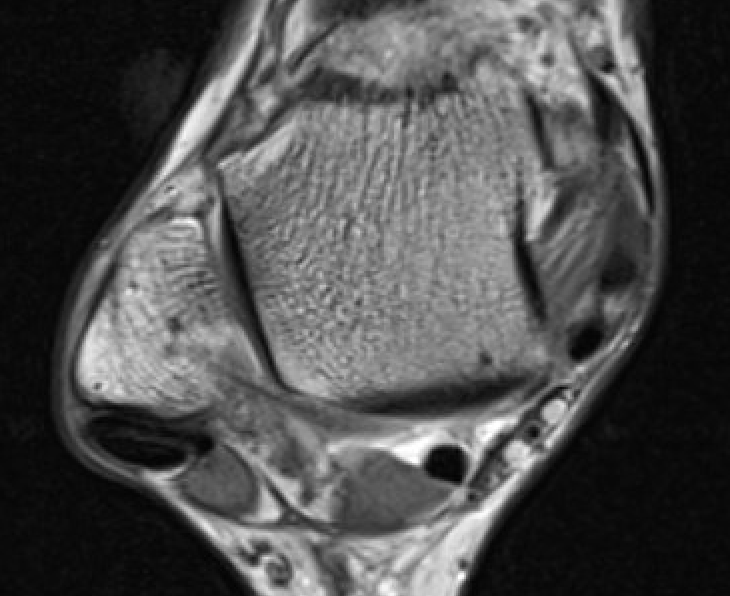

- tendinopathy - tendon thickening

Tendinopathy - thickened PL